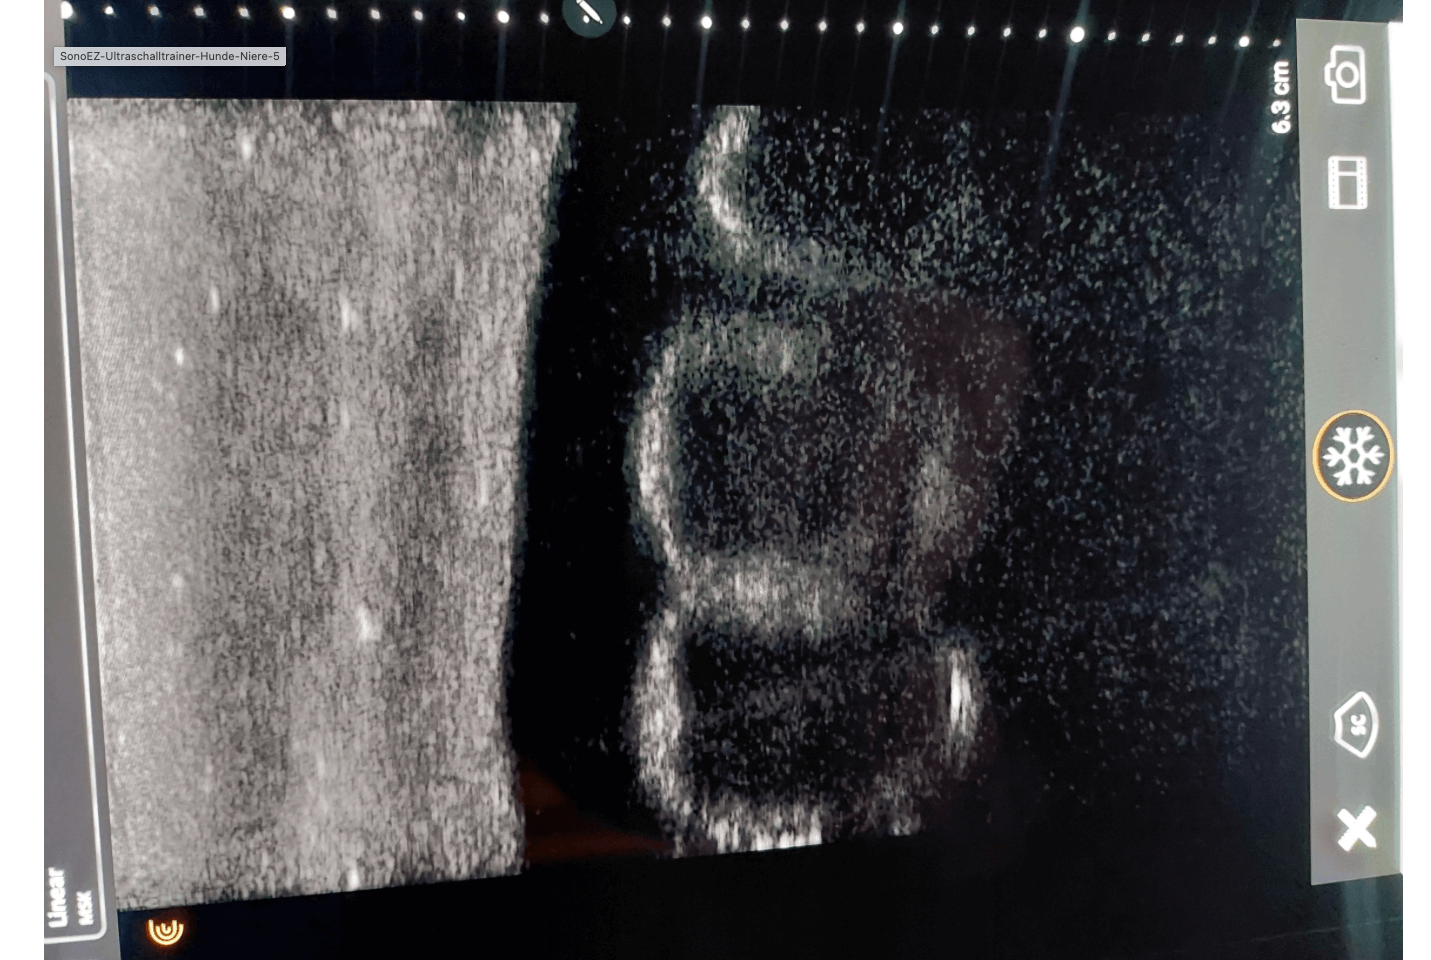

The SonoEZ Canine Kidney Ultrasound Trainer provides a practical platform for practicing canine kidney biopsies. The model includes a medium-sized tumor that can be precisely punctured to practice extracting abnormal cells. It allows students to refine their biopsy technique and learn kidney anatomy. Using advanced, ultrasound-compatible materials, this simulator delivers realistic ultrasound images, enabling effective training in sonography and biopsy.

Realistic ultrasound images : Provides detailed representations of the dog's kidney and any tumor it contains.

Anatomical accuracy : Supports the formation of the kidney and its structures under realistic ultrasound conditions.